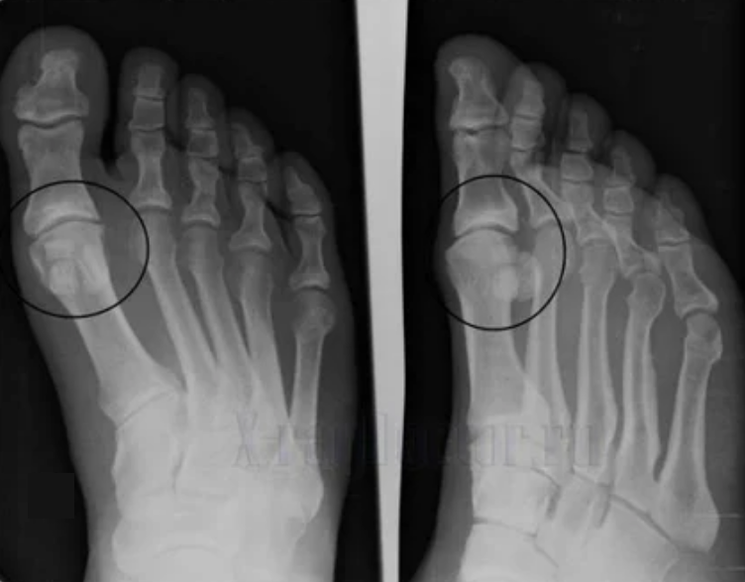

Fir eng Diagnos ze maachen, rheumatologen de Reklamatioune vun der Patient ze studéieren an eng x -rayprüfung virschreiwen. Meeschtens, Radiographie gëtt an 2 Projektiounen benotzt. Den Dokter kuckt op d'Präsenz vu dystrophesche Stéierungen an Hyaline Knorpel an Schanken. Wann de artikuläre Spalt reduzéiert gëtt, sinn deforméiert oder flaach, et sinn zäitscht Formulairen vun der Uewerfläch vum Cargetage, Osteophyten sinn offensichtlech Zeeche vun Arthrossis. Wärend der Inspektioun, Arthrosis weist d'Onstabilitéit vum Gelenk: d'Achs vun de Glieder a Surperuxatioun ass gestéiert.

Dacks ass en x -raybild net fäeg fir komplett Informatioun iwwer d'Konditioun vum Gelenk ze ginn. Fir eng méi grëndlech Etude, berechent d'Zommographie gëtt verschriwwen, et ass effektiv fir d'Schanken ze ënnersichen. Mri ass méi dacks benotzt fir mëll Stoffer ze studéieren.